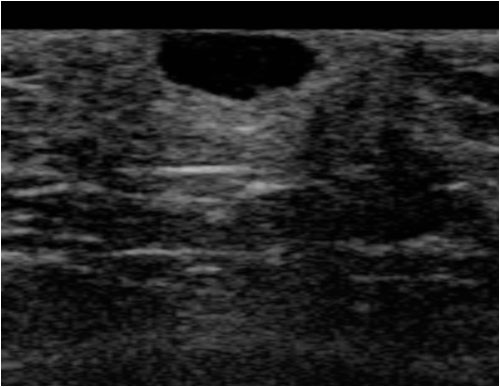

위 사진은 핀홀법 수술 직후 촬영한 사진입니다.

초음파 검사를 통해서

피지 및 주머니 상태를 파악할 수 있고

낭종의 범위와 깊이를 추측할 수 있습니다.